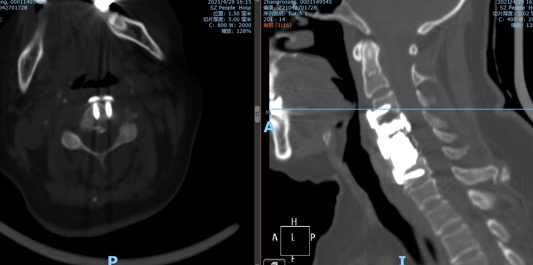

此为张阿姨术前颈椎CT骨窗,可以看见张阿姨的颈椎出现了被肿瘤破坏,侵蚀的表现。

此为张阿姨手术后的CT图像,可以看见张阿姨的椎体被骨水泥填充的同时,也进行了内固定处理,这样做不仅缓解了疼痛、破坏了肿瘤细胞,同时也对颈椎起到了强有力的固定。保持其稳定性。